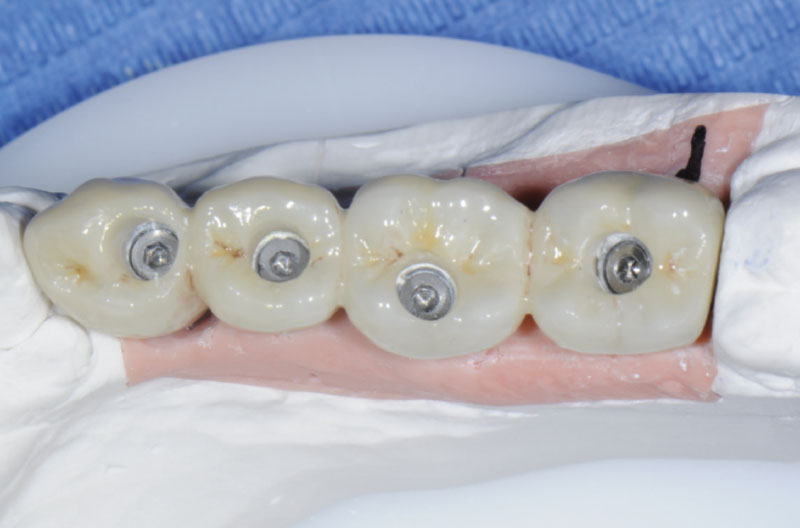

Fig. 19 – Avvitamento del ponte sui monconi MUA

Fig. 20 – Vista occlusale del ponte avvitato

Figg. 21, 22 – Ponte in situ dopo la chiusura dei canali vite

Fig. 22